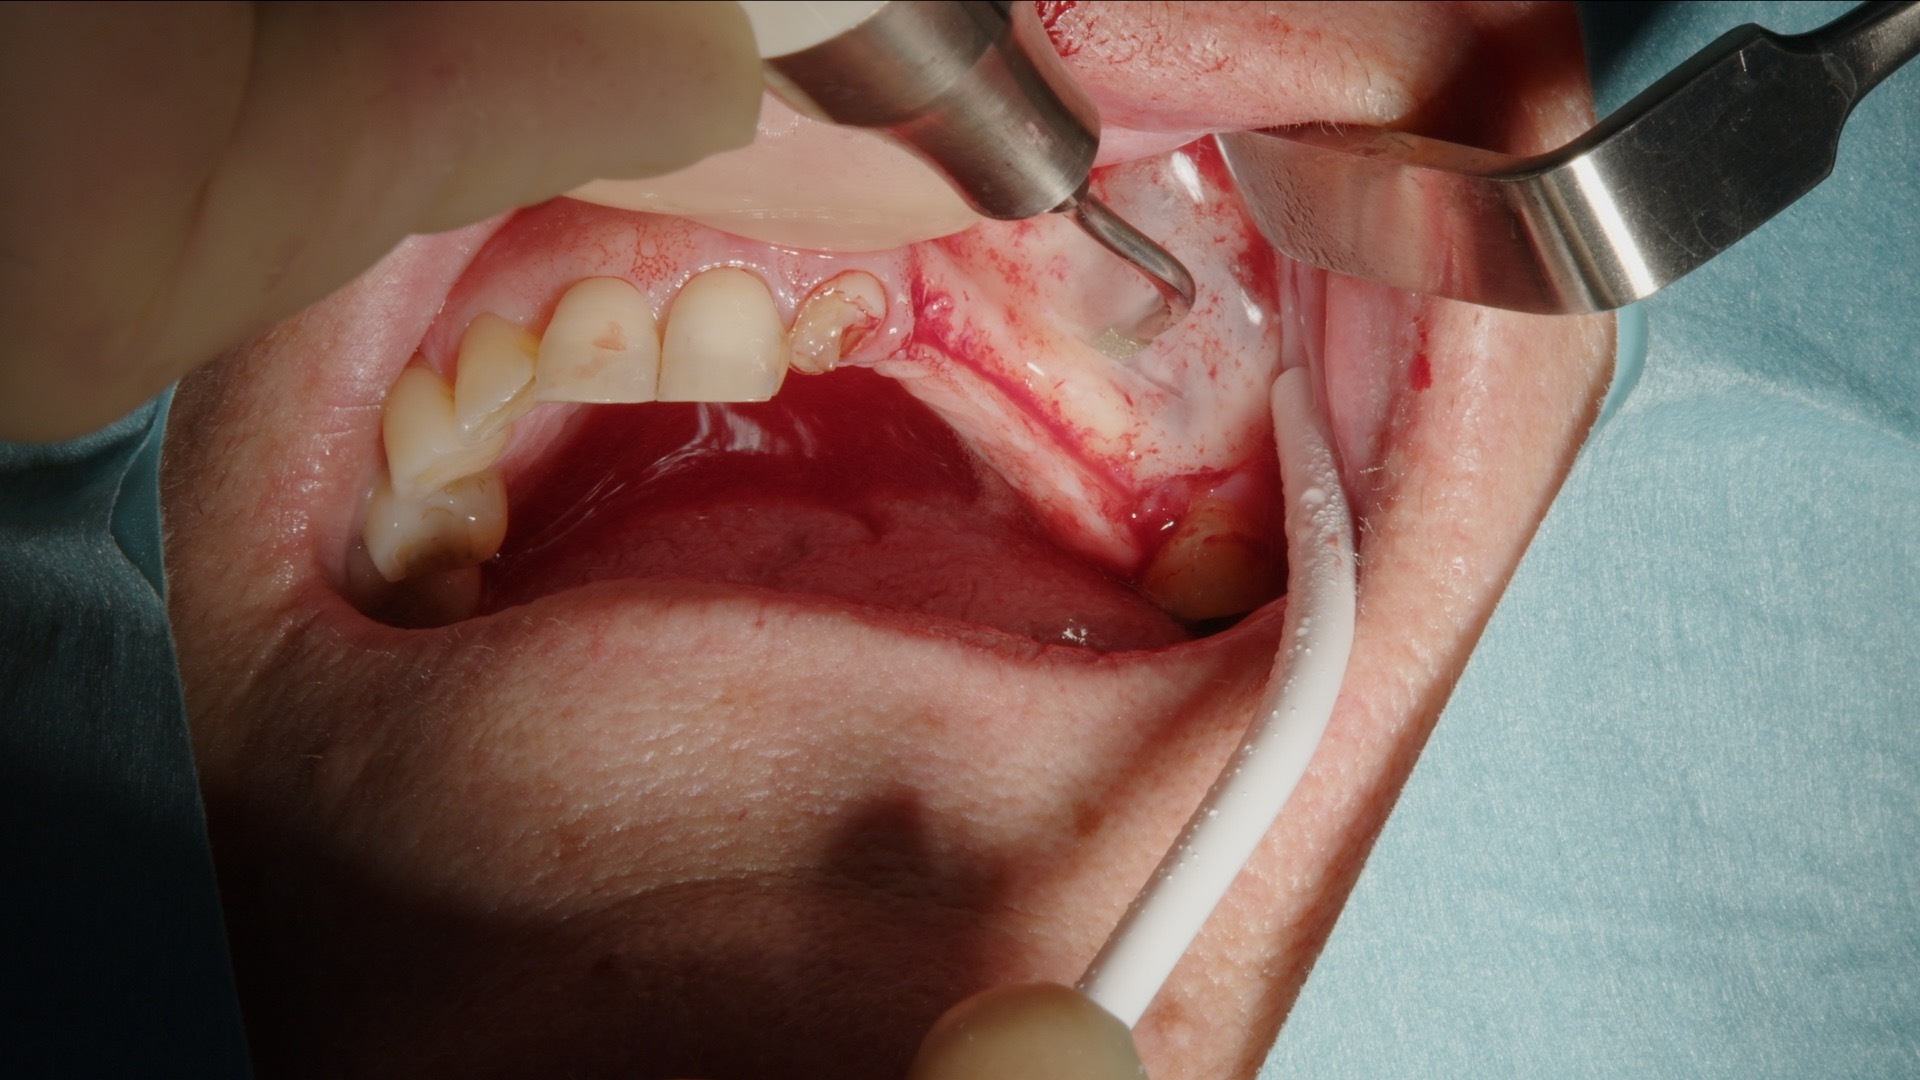

2. Preparering av lateralt fönster med Acteon Piezo Cube och diamantspets.

3. Skonsam elevation av sinusmembranet med piezo-lyftspets.

Det laterala fönstret prepareras konsekvent med Acteon Piezo Cube och diamantspets. Den piezoelektriska tekniken möjliggör selektiv benbearbetning med hög precision och minimal risk för skada på mjukvävnad och sinusmembran. Instrumentet är ergonomiskt, lätt att manövrera och ger god taktil kontroll, vilket bidrar till ett effektivt och tryggt arbetsmoment.